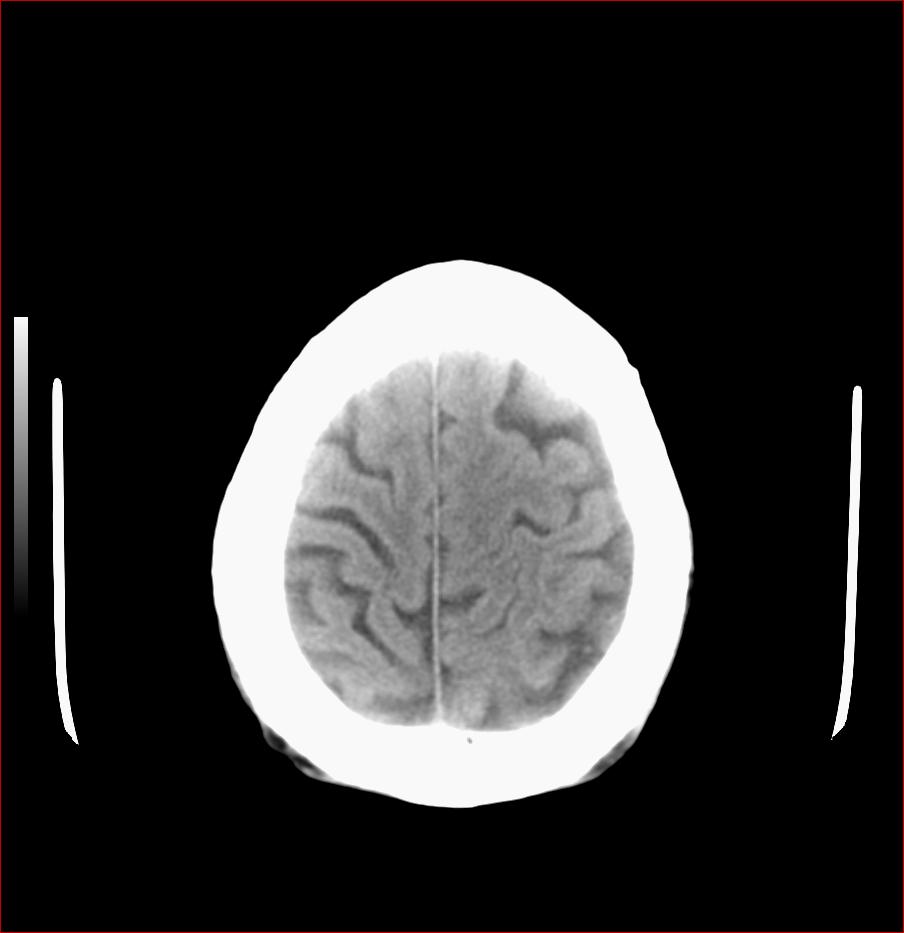

男,84岁,左下肢无力伴口角歪斜1天,血压160/80。请问一下双侧基底节区是脑梗塞吗?

老年性三联症_多发腔隙性梗死 脑萎缩 脱髓鞘变性.

1.两侧基底节区及右顶深部脑梗塞。2.右侧外囊区脑软化灶。3.脑萎缩。4.脑白质脱髓鞘改变。

1 两侧基底节区脑梗塞;

2 右侧壳核区脑软化灶;

3 脑白质脱髓鞘;

4 脑萎缩。